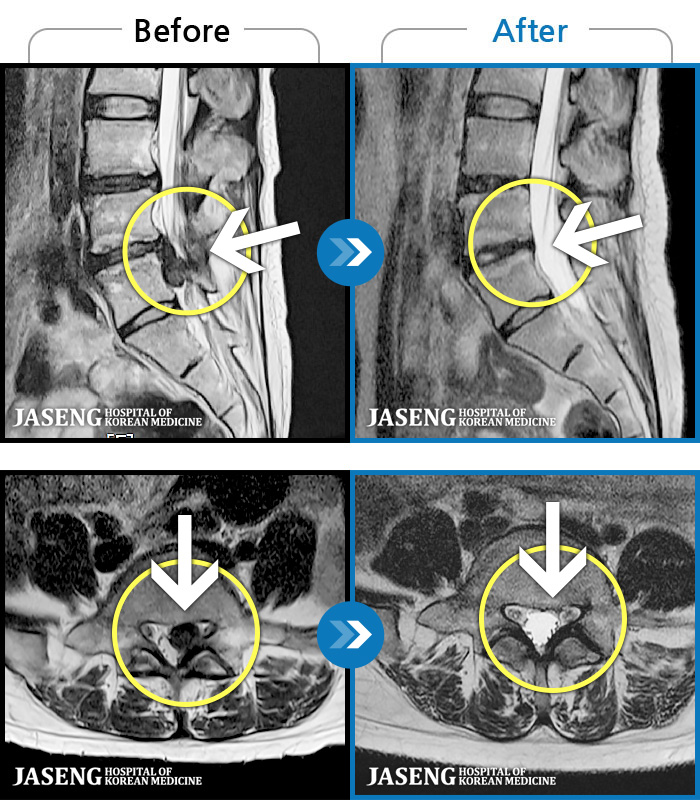

허리디스크

인천 · 조남훈 원장

좌측 허벅지와 종아리가 찌릿하고 묵직한 통증이 있어요.

촬영시기

2025.03.18 ~ 2025.07.22

2025.08.01